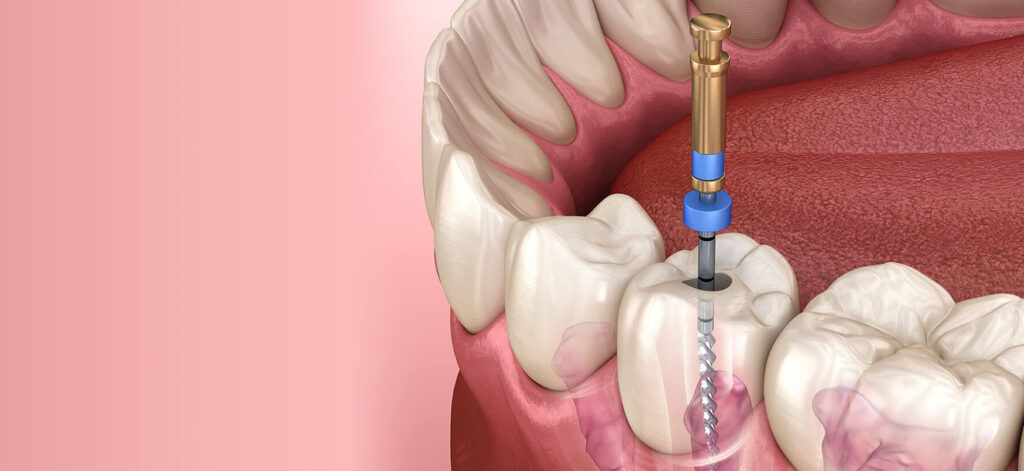

Kanal Tedavisi (Endodonti)

Dişin içindeki pulpa (sinir, damar paketi) iltihaplandığında veya enfekte olduğunda uygulanır. Bu tedavi ile dişin çekilmesine gerek kalmadan ağızda tutulması sağlanır.

6) Kanal tedavisi sonrası dişim zayıflar mı?

Pulpa çıkarıldığından kırılganlık artabilir; uygun onlay/kronla desteklenirse uzun yıllar işlev görür. Mikroskobik çalışma sızıntı riskini azaltır.

Kanal tedavisi başarısız olursa? Retreatment veya apikal cerrahi seçenekleri vardır.